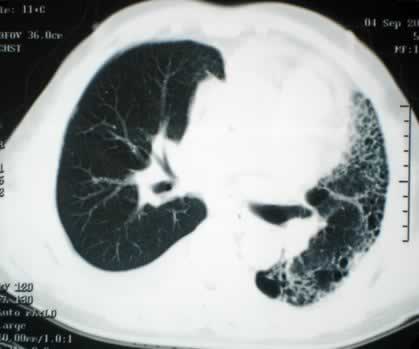

1986年10月28日,西班牙潘普洛纳市纳瓦拉大学医院成功地进行了一次心脏和肺脏同时移植手术。这一手术在西班牙是第一次。

接受心肺植入手术的是十三岁的女孩阿尔穆德纳-加尔韦斯,她因双肺纤维性病变,呼吸十分困难。这家医院心血管外科专家二十七日午夜开始对女孩施行移植手术,手术复杂艰难,持续到二十八日凌晨四点。据手术医生说,手术后女孩感觉良好。

植入女孩的心脏和肺脏取自一位十一岁的男孩,他是不幸因脑颅创伤死亡的。